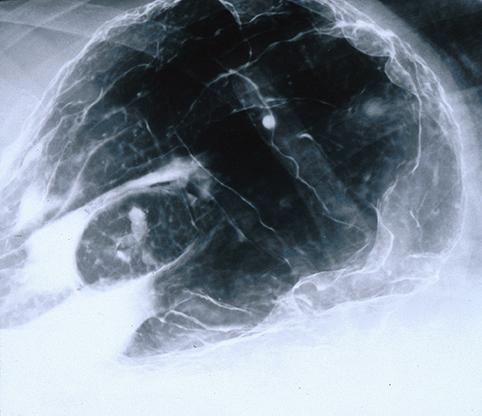

Tumor Maligno de Linfoma que muestra lesión de tubos digestivos de tipo MLP(Multiple Lymphomatous Polyposis) inclusive del esófago

[Image-ID:6817]

Linfoma Maligno/Linfoma Maligno tipo MLP

estómago(región)/fornix

Rayos X

30 - 34

presente(simultáneo-metacrónico)